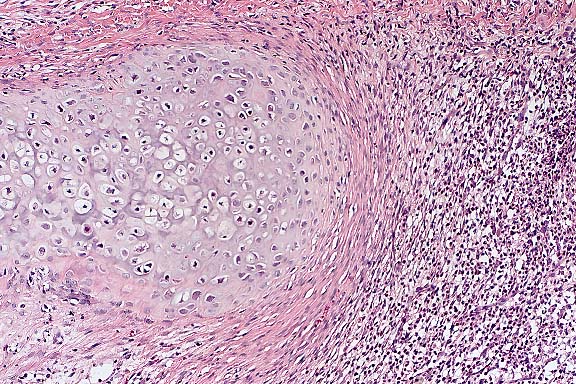

Case 27-1. Lip. The inner surface shows a vesicle containing necrotic acanthocytes and multincleated syncytial cells with diffuse, vague amphophilic nuclear inclusions. 20X

1. Dermatitis, vesicular, acute, multifocal with epithelial syncytial cells and eosinophilic intranuclear inclusions.

In contrast to the gross skin lesions, the microscopic lesions are relatively mild and include degeneration and necrosis of surface and adnexal epithelium and vesicle formation. Intranuclear viral inclusions are present in almost all affected epithelial foci. A mild variable neutrophilic infiltrate and multifocal subcuticular hemorrhage are present in the dermis of some affected sections. In sections with subcutaneous hemorrhage, small vessels are congested, lined by rounded endothelium and contain occasional fibrin aggregates. Some vessel walls are necrotic and rare endothelial cells contain intranuclear inclusions. Similar vascular lesions are present in the spleen.

1. Lip: Degeneration and necrosis, epithelial, multifocal, with vesicles, syncytia, vasculitis, and epithelial and endothelial eosinophilic intranuclear inclusion bodies, cynomolgous monkey (Macaca fascicularis), primate.